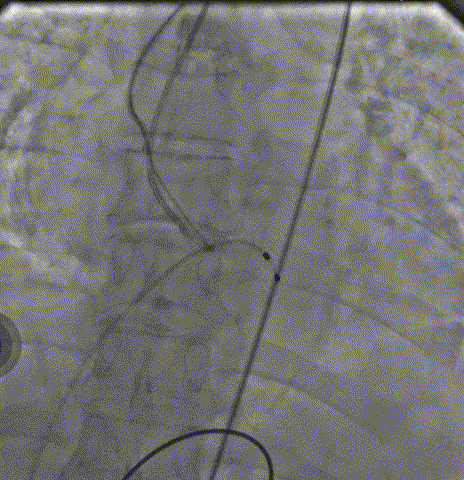

导丝顺利跨瓣